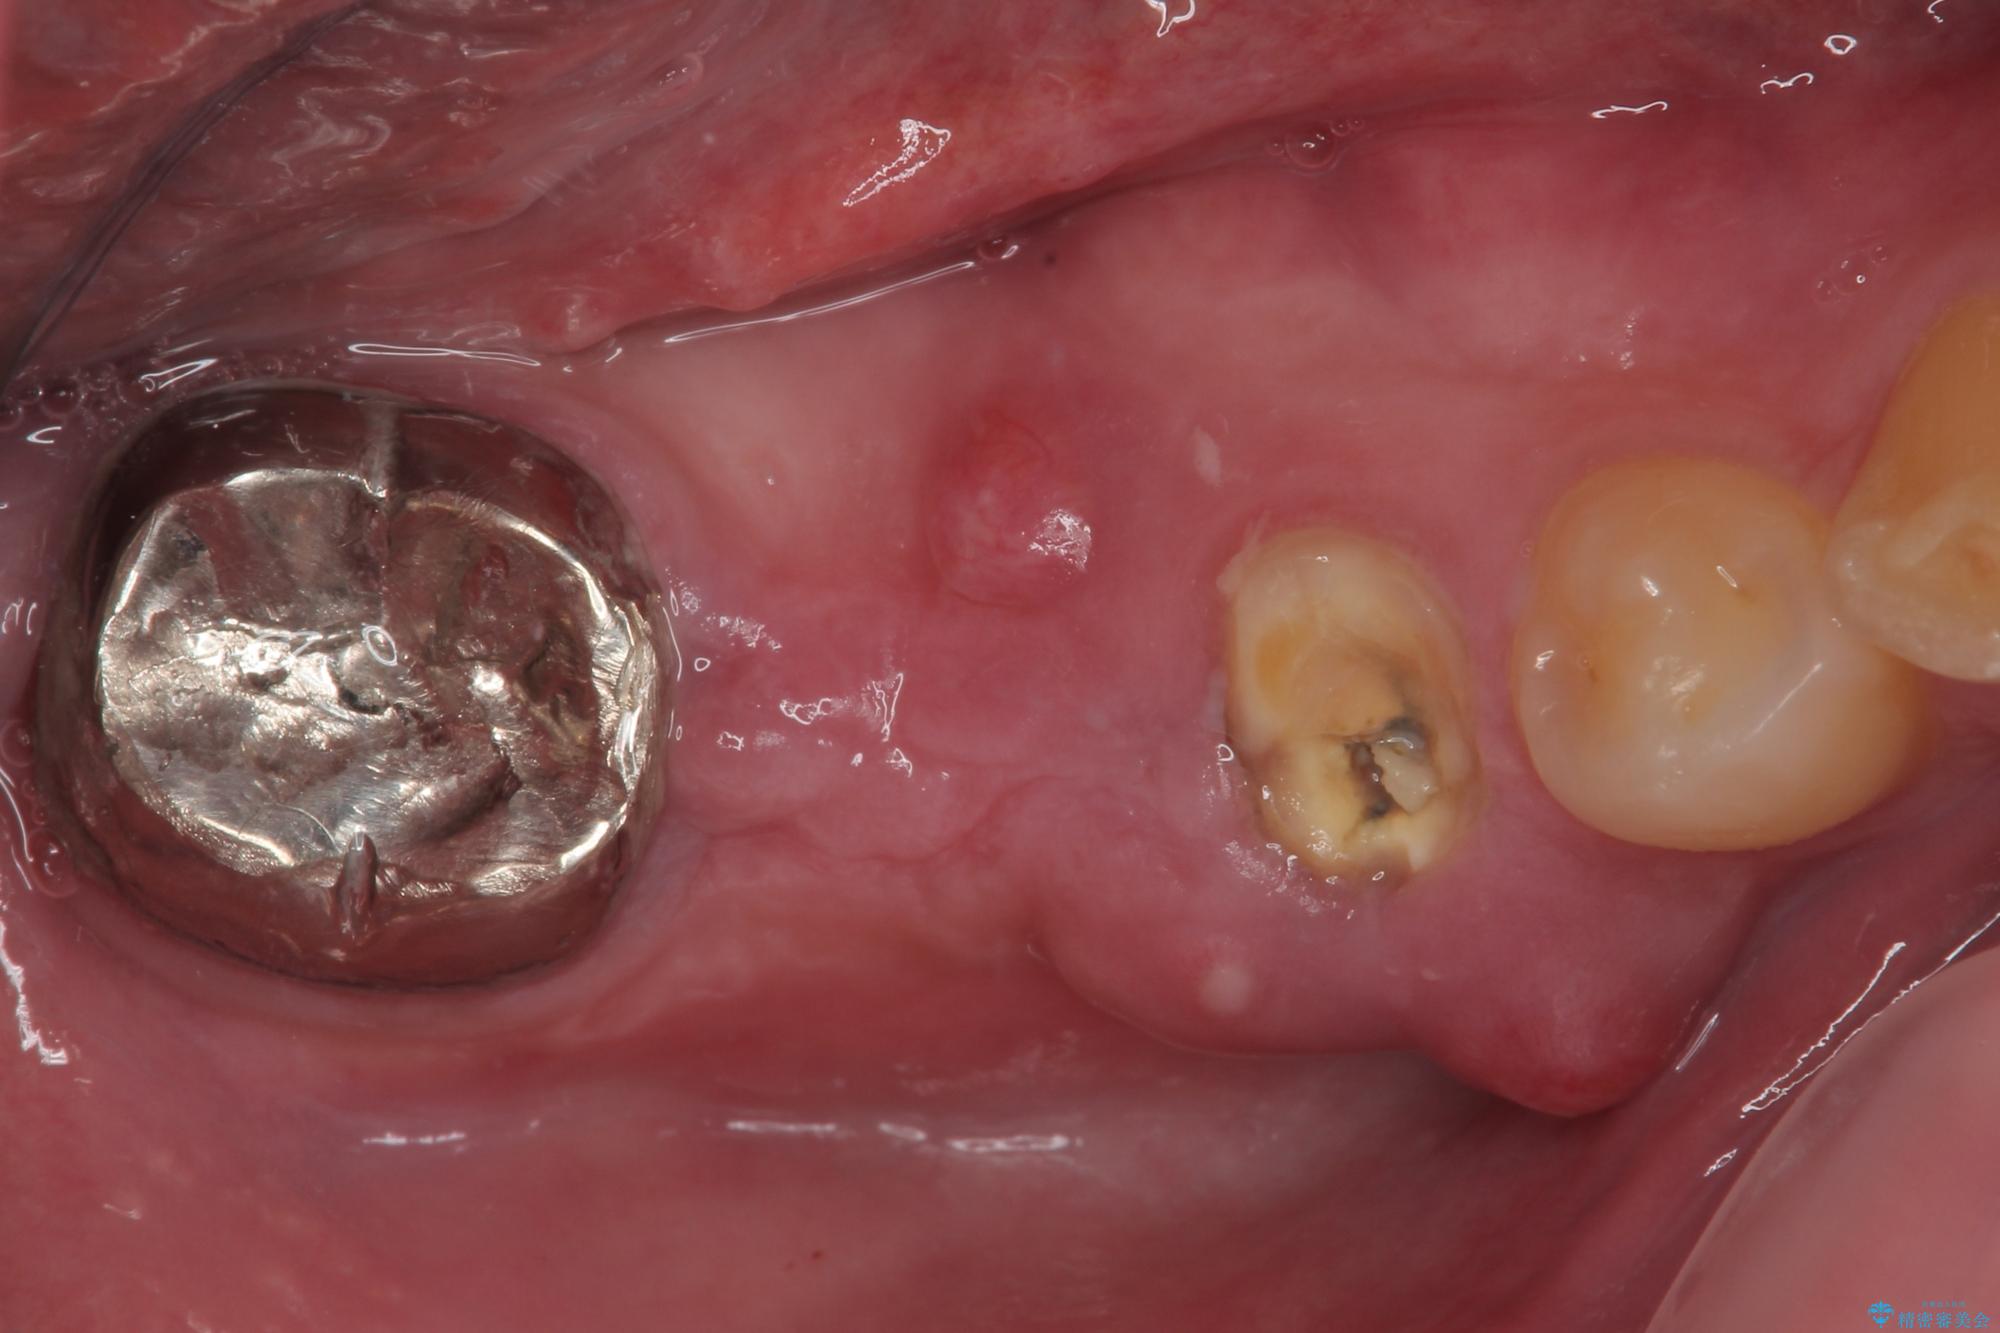

- むし歯を放置したことで、歯茎で膿が腫れ上がったしまったとのことで来院された患者様です。

ブリッジの支台歯が痛みを覚え、近医でブリッジを切断してもらって以降、そのままにしてしまったとのことでした。

問題が起きていた手前の歯から膿が出てきたことを自覚して当院を来院されましたが、既に歯根破折をしており、抜歯が必要な状態でした。

咬合力が非常に強い患者様であり、2歯欠損のブリッジ(しかも大臼歯は失活歯)は歯根破折のリスクが高すぎると判断し、抜歯部および欠損部に対して、インプラントによる補綴治療を行うこととしました。